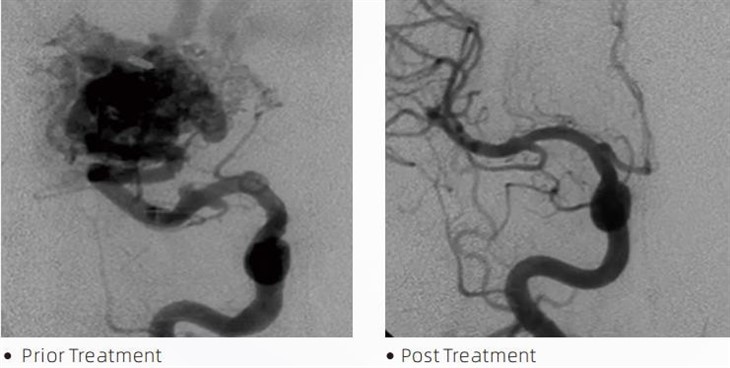

LaavaTMemboolne liim on meditsiiniseade, mida kasutavad sekkuvad neuroradioloogid minimaalselt invasiivsete protseduuride ajal selliste seisundite raviks nagu ajuaneurüsmid, arteriovenoossed väärarengud ja kasvajad. Lava emboolia liim pakub nii meditsiinitöötajatele kui ka patsientidele mitmeid eeliseid ohutuse, kasutuslihtsuse ja tõhususe osas. Laava suudab veresooni kiiresti ja tõhusalt sulgeda. Protsess hõlmab liimi süstimist otse sihitud anumasse, kus see polümeriseerub ja kõveneb valutaoliseks massiks, mis täidab aneurüsmi või väärarengu. Seejärel katkestab see tõhusalt kahjustuse verevoolu, vältides selle rebenemist ja vähendades püsiva kahjustuse või insuldi riski. Lava hõlmab Lava-12, Lava-18 ja Lava-34. Iga ravimvorm on loodud konkreetsete kliiniliste vajaduste rahuldamiseks. Lava-18 on tavaliseks kasutamiseks mõeldud standardpreparaat. Lava-34 on suure viskoossusega liim suure vooluga anumatele. Kuigi Lava{7}} on madalama viskoossusega ja voolavam, võimaldades distaalseid mikrosooneid. Nende võimaluste abil saavad sekkuvad neuroradioloogid valida sobivad Lava koostised, et tagada optimaalsed tulemused. Lava üks tähelepanuväärsemaid omadusi on selle mittekleepuvad omadused. See aine on spetsiaalselt valmistatud nii, et see püsiks stabiilsena kuni sihtpiirkonda jõudmiseni. See omadus tähendab, et Lava emboolia liimi saab täpselt arterisse asetada ja sinna jääda ilma ümbritseva koega kleepumata või sidumata.